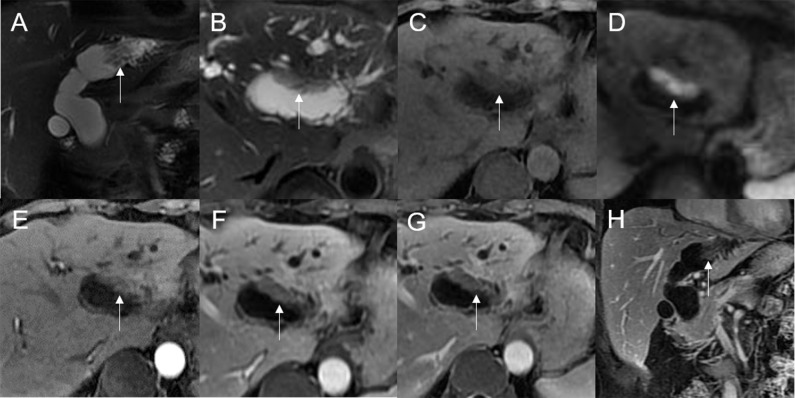

Mean lesion size in the whole sample was 30.83 ± 20.93 mm. All patients presented with an intraluminal ductal mass. While 14/32 (43.75%) lesions presented morphologically as focal eccentric-type masses (f3), 9/32 (28.13%) presented as plaque-like masses, 4/32 (12.50%) as bile duct casting masses, and 5/32 (15.62%) as infiltrative masses. In addition, 8/32 (21.88%) lesions showed a frond-like superficial appearance accompanied by other morphologically categorized appearances other than plaque-like superficial (f4, f5; T2).

On standard MRI scanning, 24/32 (75%) lesions showed hyperintensity and 9/32 (25%) showed isointensity on T2WI, while 9/32 (28.12%) lesions showed isointensity and 23/32 (71.88%) showed hyperintensity on T1WI. In addition, 3/32 (9.38%) lesions showed speckled hyperintensity on T1WI (f7).

On dynamic enhanced MRI, 14/18 (77.78%) lesions showed moderate enhancement, 2/18 (11.11%) showed obvious enhancement, and 2/18 (11.11%) showed slight enhancement. While 13/18 (72.22%) lesions showed stable and persistent enhancement, 5/18 (27.78%) showed wash-in and wash-out enhancement (T2).

On DWI (b = 800 s·mm-2), 5/32 (15.63%) adenomas showed isointensity (f2) and 27/32 (84.37%) showed hyperintensity. In 2/32 (6.25%) cases, the bile duct wall around the lesion showed hyperintensity on DWI (f8). The mean ADC value of the lesions was 1.65 ± 0.38 × 10-3 mm2·s-1 (T2).